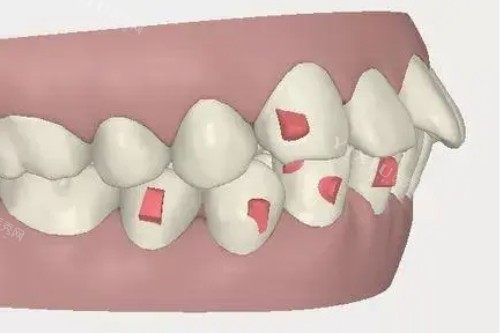

2. 牙齿矫正项目

• 金属自锁托槽矫正:9800元起,较高的效率更准一些,复诊间隔长,经济实用型选择。

• 时代天使隐形矫正:18800元起,国产隐形矫治领军品牌,更准一些控制牙齿移动,舒适度优于传统托槽。

• 儿童早期干预矫正:针对3-12岁儿童错颌畸形进行预防性矫治,避免后期复杂矫正。